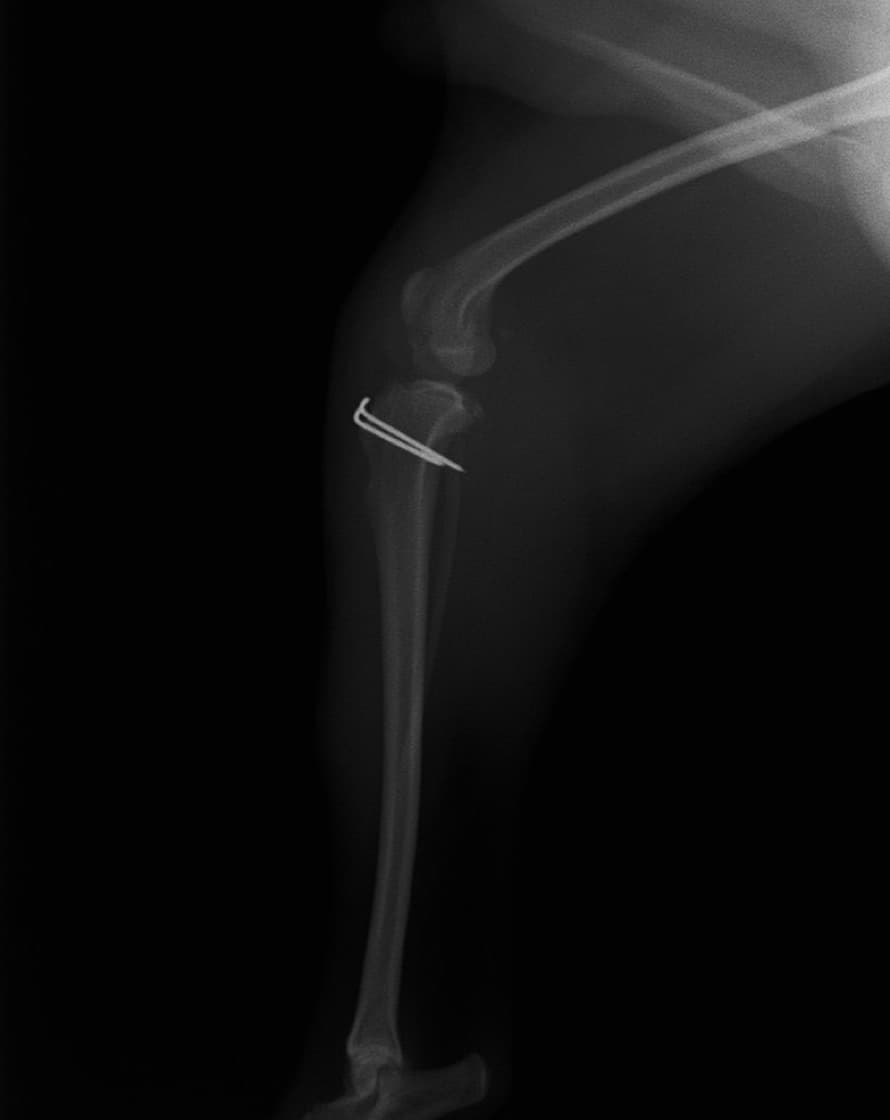

■ 症例22 ポメラニアン 1歳5か月 去勢雄

左後肢の挙上を主訴に来院した。整形学的検査、レントゲン検査より左右の膝蓋骨脱臼(左GradeⅡ〜Ⅲ、右Grade Ⅱ)を認めた。また、脛骨の前方引き出し試験の際に、引き出し兆候は認められないものの、疼痛が認められたため、前十字靭帯の損傷が疑われた。術中における、目視および関節内の操作によって、前十字靭帯の損傷や過伸展といった異常が認められなかったため、膝蓋骨脱臼の整復のみ実施した。手術手技は縫工筋及び内側広筋の解放、脛骨粗面の外側転位、滑車ブロック形造溝術、内外側関節包の縫縮を実施した。本症例は跛行もなく経過良好である。しかし、頸骨高平部の角度(TPA)が 右26.2°、左24.9°であり、解剖学的に前十字靭帯損傷のリスクが高いことから今後の経過に注意が必要である。